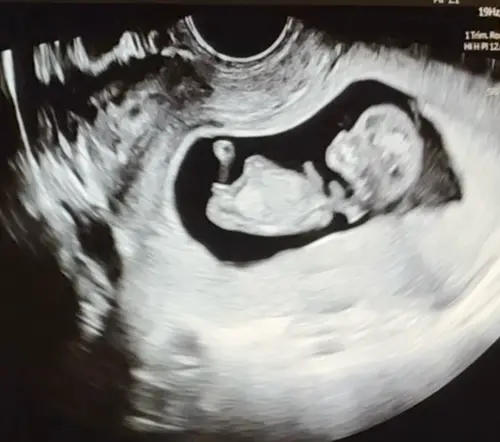

Ik vind het zo knap dat mensen hier wijs uit komen, ik kom er zelf maar niet uit, maar ben stiekem ook wel benieuwd of onze 2de een jongen of meisje is, kan iemand helpen? 😊

Alvast bedankt !

Wellicht dat ik hier tussen kom haha.. ziet iemand wat het is?😂

Duidelijk meisje!